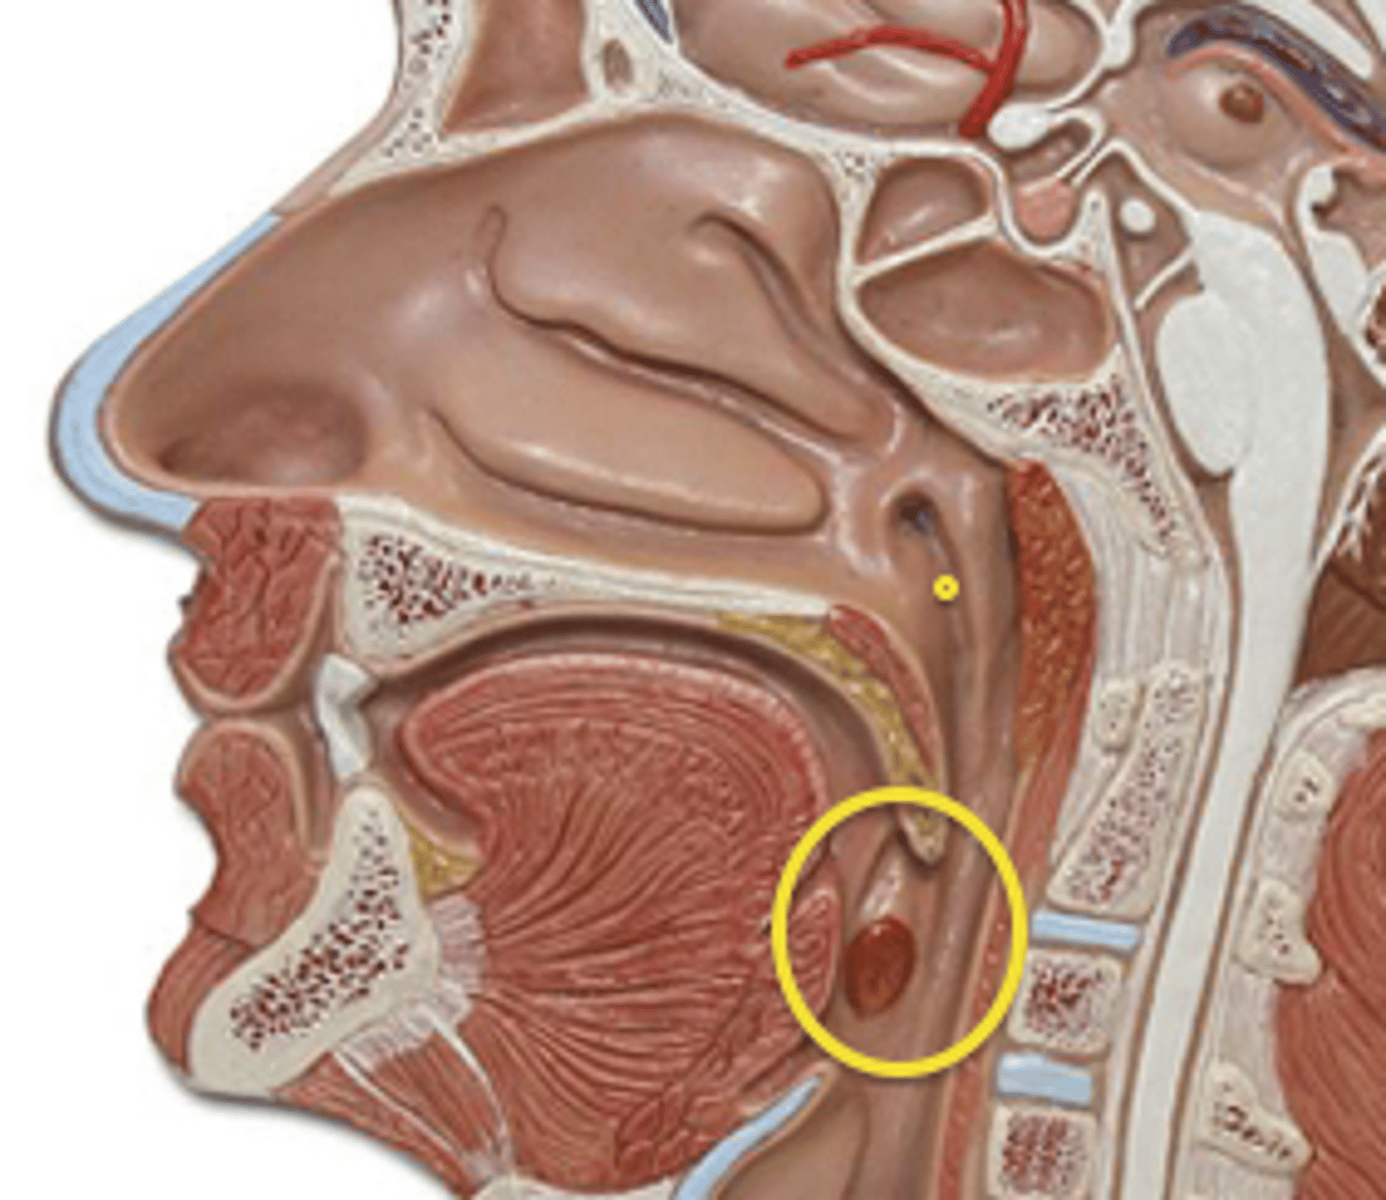

Pharynx (Throat)

Passageway for air, leads to trachea

Function of Throat

- Passageway for food

- Passageway for air

- Tonsils are part of the immune system

Tonsils

Masses of lymphatic tissue in the back of the oropharynx

3 Tonsils in the Mouth

- Palatine

- Adenoid

- Lingual

Palatine Tonsil

One of a pair of almond-shaped masses of lymphatic tissue in the oropharynx

Adenoid Tonsil

Pharyngeal tonsil

Lingual Tonsil

Tonsil located at the base of tongue